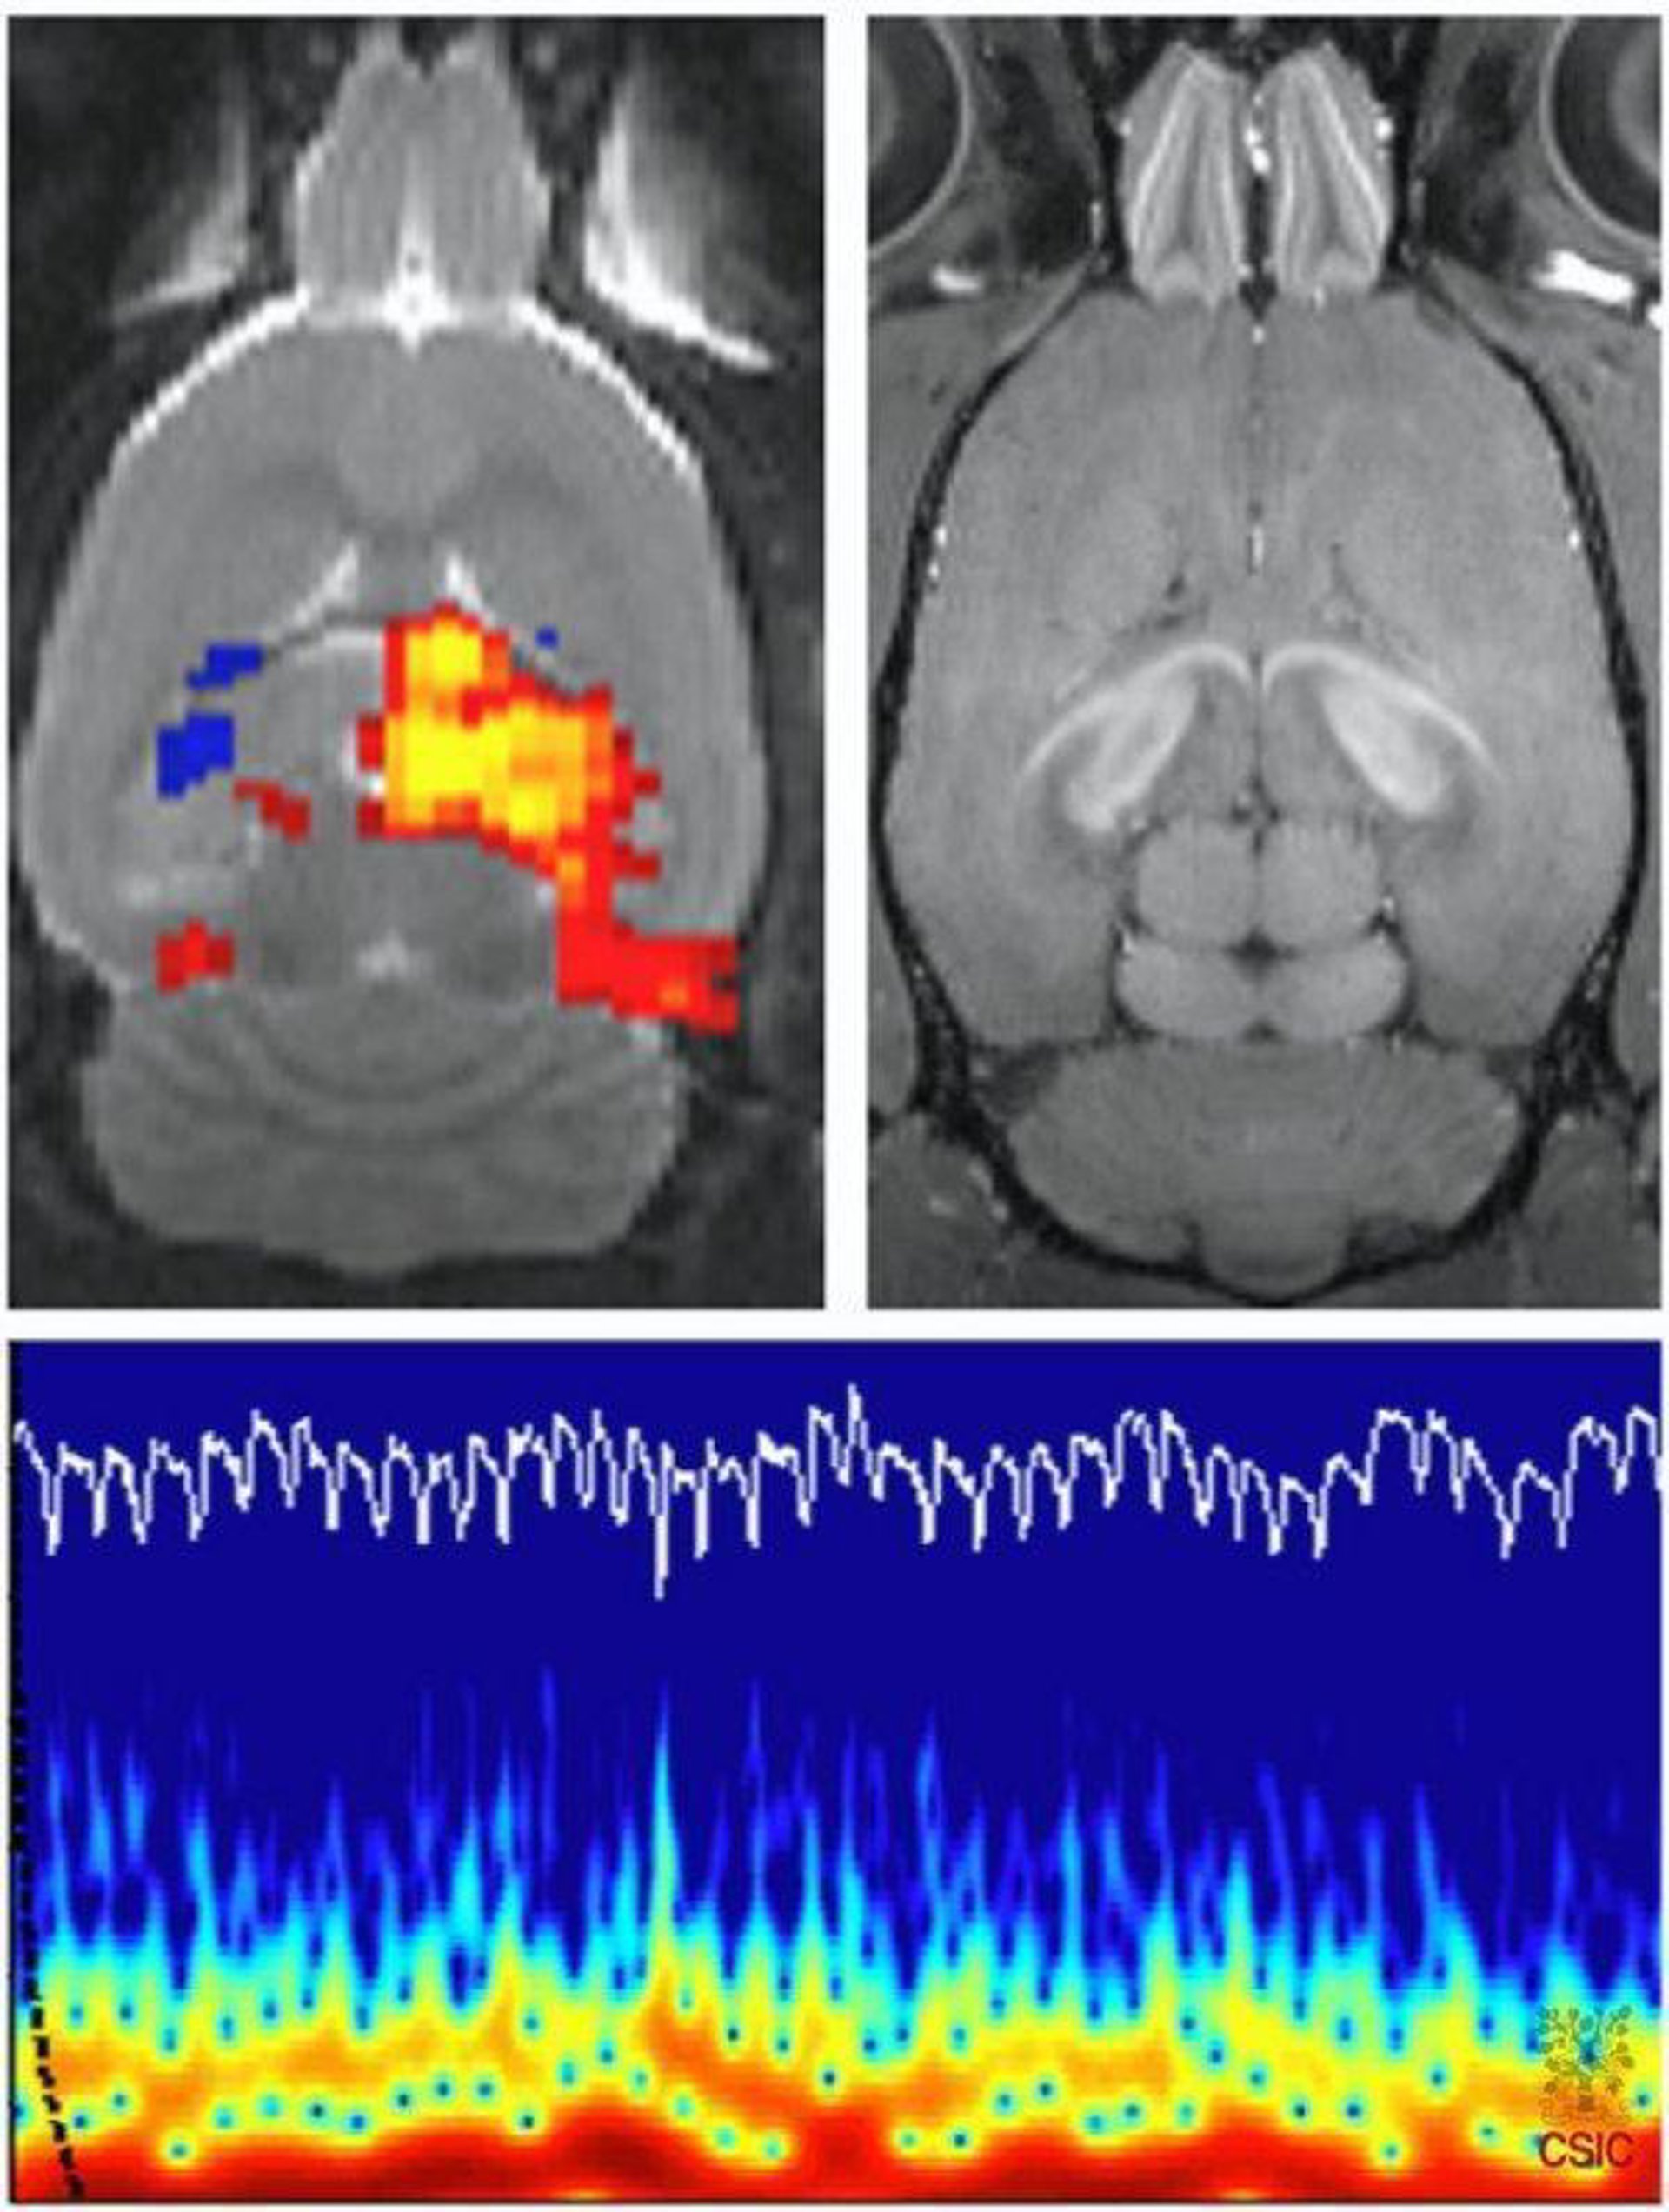

La información facilitada por el sistema, que emplea un campo magnético de 7 Teslas --unas 140.000 veces el campo magnético de la Tierra--, permitirá convertir al instituto en el segundo centro en el mundo con capacidad para investigar las bases neurofisiológicas de la resonancia magnética funcional, aún sin esclarecer.

Según informó el Centro de Investigaciones Científicas en su página web, todos los sistemas de resonancia magnética nuclear emplean un campo magnético potente y secuencias pulsadas de radiofrecuencia para traducir, mediante un software y un hardware determinados, estas señales en imágenes detalladas de órganos vitales o tejidos blandos.

Estos aparatos pueden obtener imágenes de actividad cerebral, y por tanto, identificar regiones que participan de forma específica en la ejecución de una tarea determinada.

Uno de los primeros cometidos del dispositivo del Instituto de Neurociencias será

contribuir a determinar cuáles son los mecanismos celulares que generan la señal

de RMN funcional BOLD (acrónimo inglés de Blood Oxygen Level Dependent), que

aún son desconocidos para la comunidad científica.

"A pesar de su gran importancia para el diagnóstico clínico y la planificación neuroquirúrgica, no hemos determinado en profundidad cómo la señal neuronal se transforma en una señal vascular, que es la que recoge la resonancia", explicó el investigador del CSIC Santiago Canals, responsable de esta línea de investigación en el centro.

Para llevar a cabo este estudio, los científicos combinarán los datos de RNM

funcional con otras dos técnicas de investigación como la microestimulación cerebral

profunda y el registro electrofisiológico. En la actualidad, sólo el centro Max Planck

de Biología Cibernética (en Tubinga, Alemania) mantiene una línea de estudio

similar.

El objetivo de estos trabajos es conocer con mayor precisión los procesos neurovasculares que permiten obtener imágenes mediante RNM funcional. Con esta

información será posible realizar análisis más precisos de las imágenes, que

redundarán tanto en las investigaciones que emplean esta técnica como en las

pruebas diagnósticas, según el CSIC.